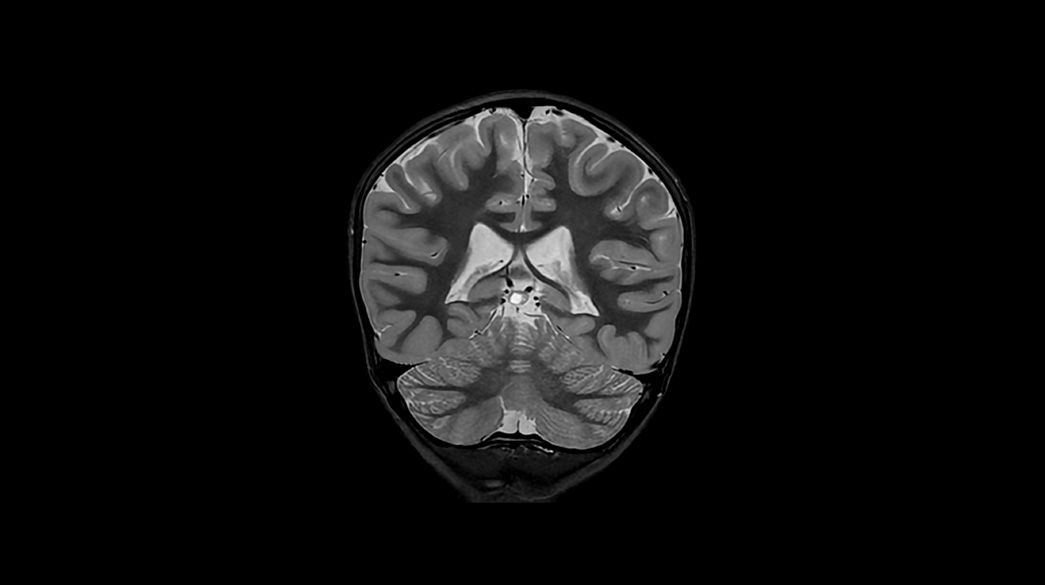

Pediatric MRI for SIGNA™

Specialized pediatric MRI protocols specifically designed to meet the needs of your smallest, most fragile patients. Provide ease of use for technologists and clinical excellence for clinicians.

Motion and distortion-reduced scans with high-resolution and contrast

Diagnostic confidence and consistency

3D-Cube-3D-MP-RAGE1040-x-585

PROPELLER1040-x-585